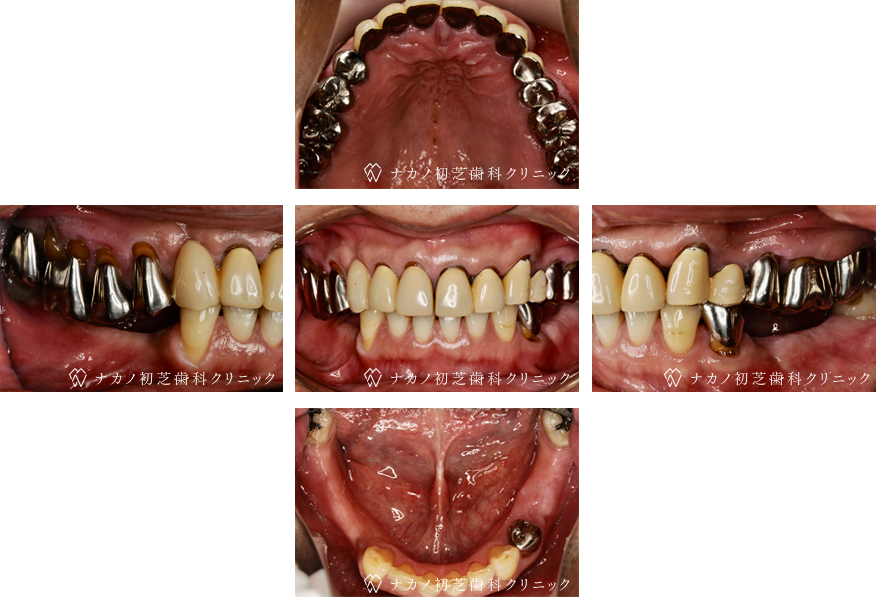

インプラント・7本 (70代男性)

BEFORE

AFTER

年齢 70代男性

治療内容 インプラント治療7本(骨造成の併用)

インプラント治療とは、歯を抜いた所にチタン製の人工歯根を埋入し、その上に歯を入れる方法です。骨を増やすことで、より審美的に治療が出来ました。費用 1本 400,000円(税込 440,000円)

リスク・副作用

腫れ・疼痛・違和感を感じるなどの症状を生じることがあります。